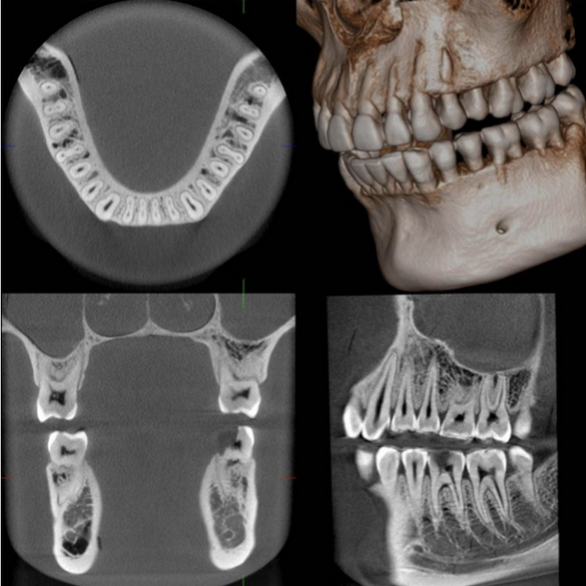

TAC FOV-16X18 y radiografía ultima generación

Una radiografía tridimensional que se toma de la boca del paciente. A partir de ella se crea una imagen virtual en tres dimensiones con las características exactas de su cavidad oral. De esta forma se facilita el diagnóstico, que además es mucho más preciso que con otras técnicas más tradicionales.